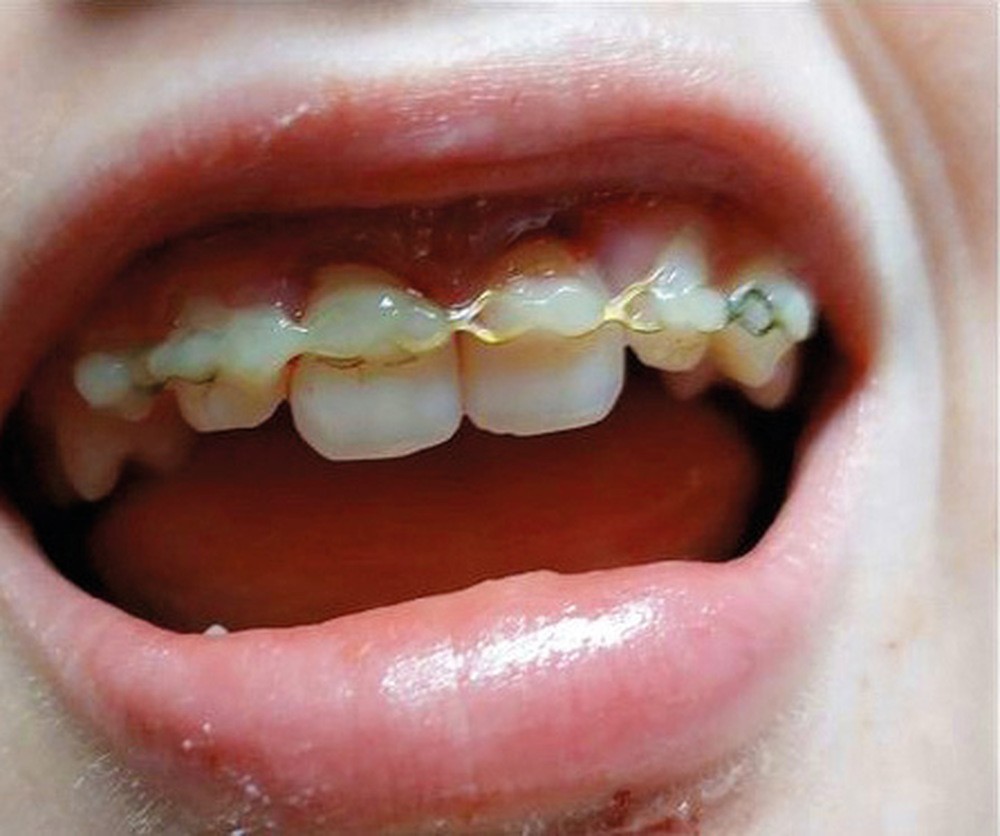

Grâce à ce cliché radiologique, une décision thérapeutique éclairée peut être prise. A savoir : la situation ne peut pas rester comme telle si l’on souhaite obtenir une guérison. Il est alors nécessaire de déposer la première contention et de repositionner convenablement les dents sous anesthésie locale aussitôt que possible puis de placer une nouvelle contention. Cela est indispensable afin d’espérer un pronostic favorable (fig. 4).

Le type de contention et sa durée de mise en place à la suite d’un traumatisme dentaire seront abordés lors de cette conférence très clinique.